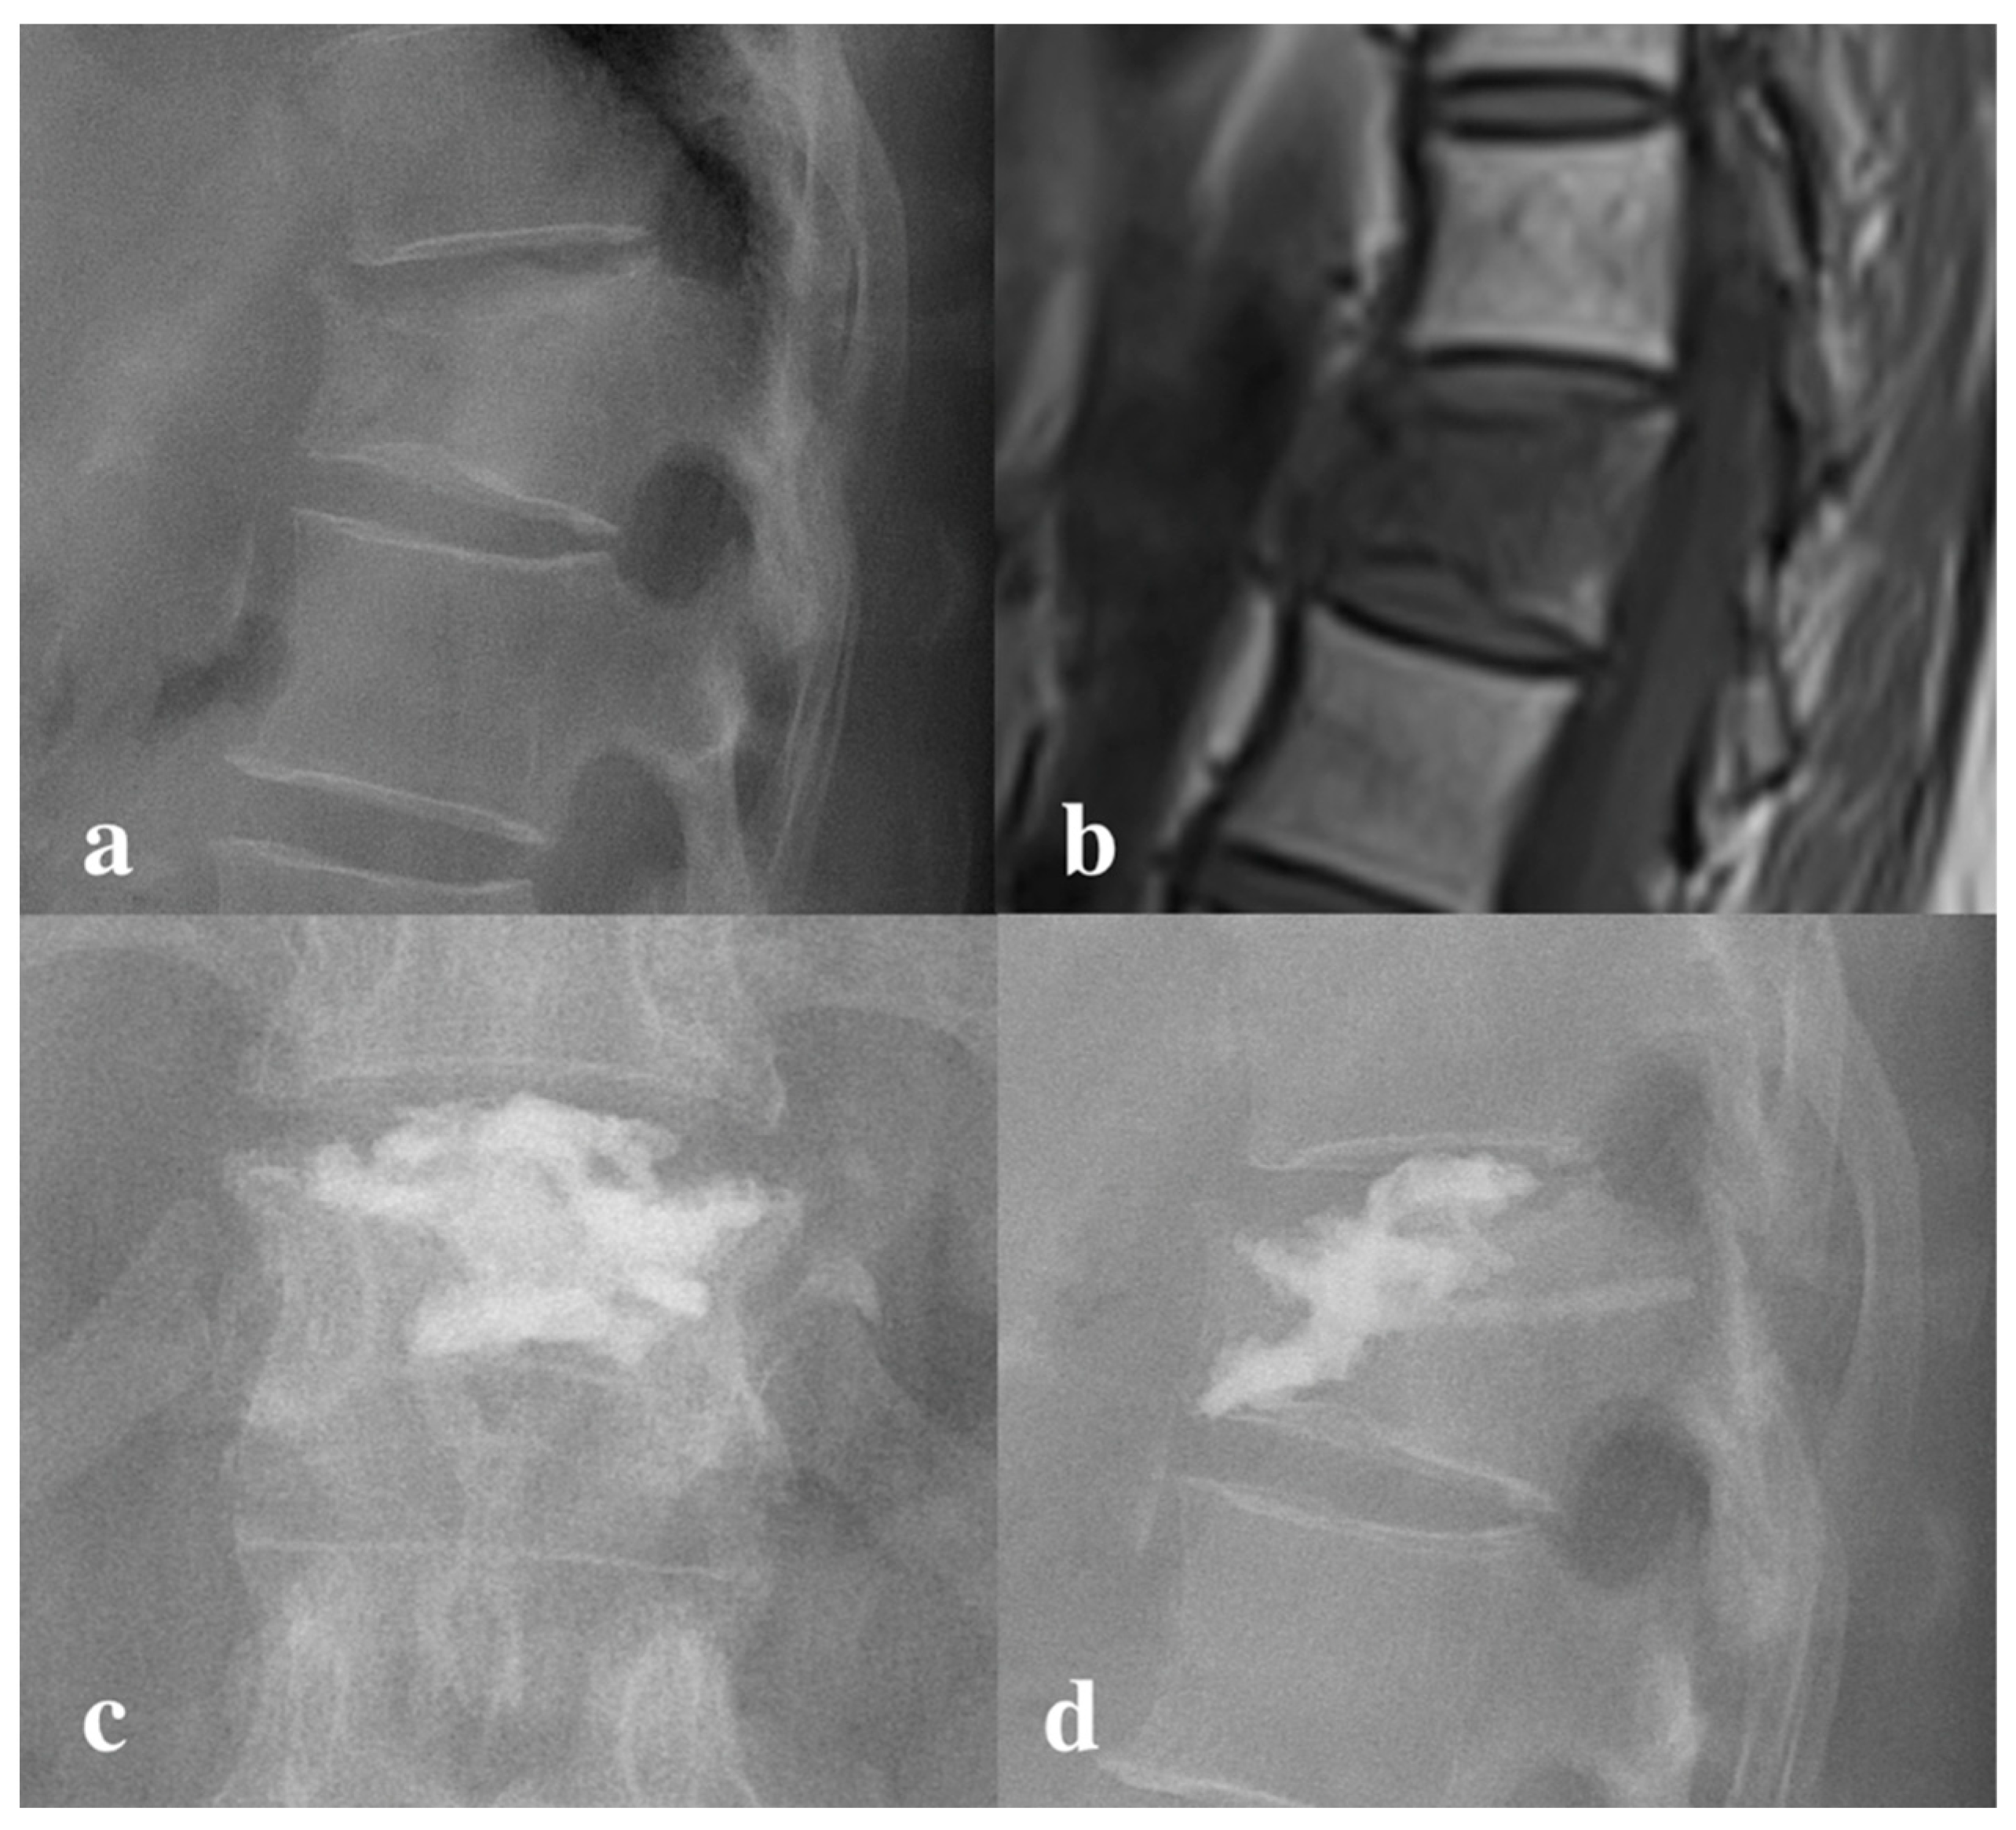

2.4.1. Decompressed Kyphoplasty

2.4.2. Vertebroplasty with High Viscosity Cement

- Chu, W.; Tsuei, Y.C.; Liao, P.H.; Lin, J.H.; Chou, W.H.; Chu, W.C.; Young, S.T. Decompressed percutaneous vertebroplasty: A secured bone cement delivery procedure for vertebral augmentation in osteoporotic compression fractures. Injury 2013, 44, 813–818. [Google Scholar] [CrossRef]

- Lu, H.T.; Lin, J.Y.; Tsuei, Y.C.; Hsu, Y.F.; Chen, C.Y.; Cheng, S.H.; Chu, W.; Li, C.; Chu, W.C. Impact of Aspiration Percutaneous Vertebroplasty in Reducing Bone Cement Leakage and Enhancing Distribution-An Ex Vivo Study in Goat Vertebrae. Bioengineering 2023, 10, 795. [Google Scholar] [CrossRef]